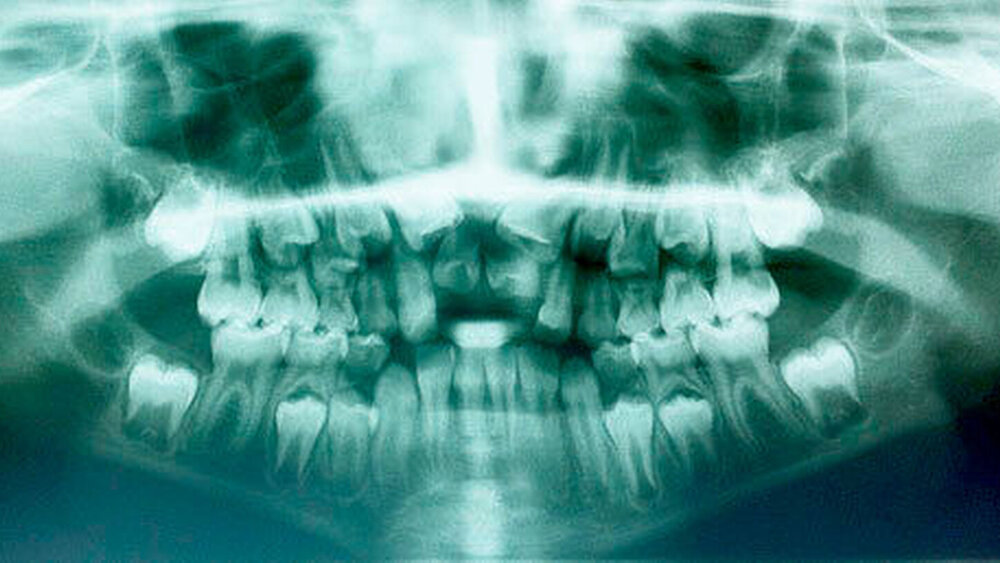

Die Prävalenz überzähliger Zähne wird im Bereich von 0,07 Prozent bis 0,6 Prozent für das Milchgebiss [Luten, 1967; Ravn, 1971; Järvinen Lehtinen, 1981; Magnússon 1984; Skrinjari Barac-Furtinovi, 1991; Yonezu et al., 1997; Chen et al., 2010] und von 0,3 Prozent bis 3,2 Prozent für die bleibenden Zähne [Luten, 1967; Bäckman Wahlin, 2001; Salcido-García et al., 2004; Leco Berrocal et al., 2007; Gündüz et al., 2008; Yagüe-García et al., 2009; Schmuckli et al., 2010; Fardi et al., 2011] angegeben. Die Mehrheit der überzähligen Zähne im Milchgebiss sind seitliche Schneidezähne im Oberkiefer, die meist mit einer normalen Morphologie und Lage durchbrechen (Abbildungen 1 bis 3) [Luten, 1967; Humerfeld et al., 1985; Garvey et al., 1999; Ferrés-Padró et al., 2009]. Der oft ungestörte Durchbruch und das Ausbleiben von Symptomen führen dazu, dass überzählige Zähne in der Milchdentition oft gar nicht diagnostiziert werden, und dies wird auch als Erklärung für die unterschiedlichen Prävalenzen überzähliger Zähne im Milch- und bleibendem Gebiss angeführt [Wang Fan, 2011]. Überzählige Zähne sind häufiger bei Männern als bei Frauen, wobei über ein Verhältnis von 1,18:1 bis 4,5:1 berichtet wird [Rajab Hamdan, 2002; Fernández Montenegro et al., 2006; Gündüz et al., 2008; Wang Fan, 2011]. In der Schweiz publizierten von Arx (1990) und Schmuckli und Mitarbeiter (2010) Geschlechterverhältnisse von 2,6:1, beziehungsweise 2,75:1. In einer aktuellen Arbeit von Mossaz und Mitarbeiter (2014) von Patienten aus dem Raum Bern lag dieses Verhältnis etwas ausgeglichener bei 1,61 zu 1.

Überzählige Zähne sind die häufigste Ursache für einen unterbliebenen oder verzögerten Durchbruch der oberen Schneidezähne (Abbildungen 13, 14, 15) [Betts Camilleri, 1999]. Besonders beim höckerförmigen Typ kommt es häufig zu Störungen der Eruption der oberen Schneidezähne [Mason et al., 2000]. Diese Komplikation macht sich klinisch initial dadurch bemerkbar, dass die oberen seitlichen Schneidezähne durchbrechen und die Eruption von einem oder beiden zentralen Schneidezähnen ausbleibt [Rajab Hamdan, 2002]. Auch in anderen Lokalisationen der Kiefer können überzählige Zähne zu Durchbruchsstörungen benachbarter Zähne führen [Garvey et al., 1999; Rajab Hamdan, 2002; Mossaz et al., 2014]. Insgesamt liegt die Prävalenz für den Ausfall des Durchbruchs bleibender Zähne bedingt durch überzählige Zähne zwischen 10,2 Prozent und 61 Prozent [Tay et al., 1984; Koch et al., 1986; Tyrologou et al., 2005; Fernández Montenegro et al., 2006; Liu et al., 2007; Gündüz et al., 2008; Hyun et al., 2009; Mínguez-Martinez et al., 2012; Mossaz et al., 2014].

Überzählige Zähne können bei Nachbarzähnen von einer leichten Rotation bis hin zu einer körperlichen Verschiebung alle Formen der Lageveränderungen bewirken. Studien zeigen auf, dass etwa bei einem Drittel der überzähligen Zähne eine Verschiebung des benachbarten Zahns resultiert [Koch et al., 1986; von Arx, 1990; Tyrologou et al., 2005; Liu et al., 2007; Gündüz et al., 2008; Mossaz et al., 2014]. Tay und Mitarbeiter (1984) berichteten gar über eine noch höhere Prävalenz von 55 Prozent. Hyun und Mitarbeiter (2009) betonen, dass überzählige Zähne im Oberkieferfrontzahnbereich nicht selten auch zu einer Diastemabildung führen, was für die Therapieplanung von Bedeutung ist (Abbildungen 16 uns 17).